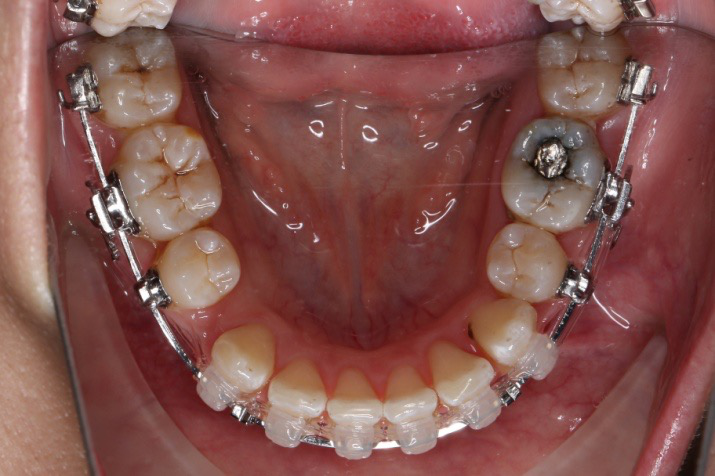

2018.04.20  间隙基本关闭,上颌重新整平,精调

2018.5.25  (19个月)拆TPA,16、26粘tube 上颌0.14*25cu-niti  下颌0.018*25niti2018.7.23  上颌 0.017*25TMA,下颌0.017*25ss43压低曲,双侧后牙垂直牵引

2018.09.29  15、43、16、17、11、21重粘,上0.016*25cu-niti 下0.018niti 上连扎

2018.11.14  术后磨牙尖牙I类关系,中线齐,覆合,覆盖正常

牙根基本平行,未见牙根吸收